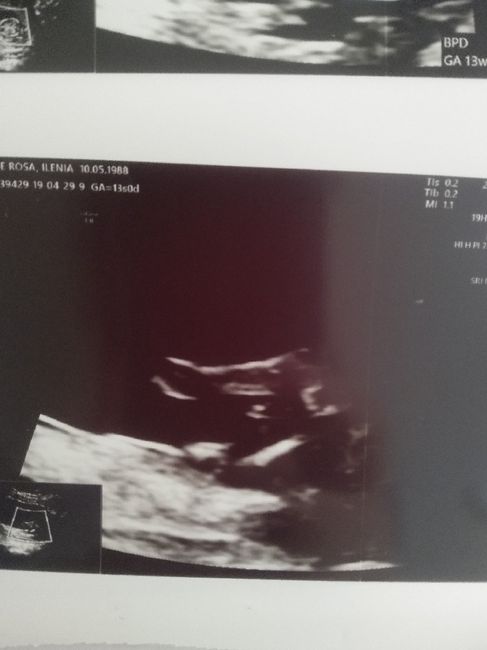

Sono stata ieri a fare la trasluceza nucale a 13+0 e mi e stato detto che e maschio al 99% e questa e l ecografia posso fidarmi?grz x le risp

Mi sa che ti puoi fidare! Anche se a 13 settimane è prestino per avere la certezza ma io aspetto il secondo maschietto e per esperienza si è visto proprio così che erano maschi anche se del primo a 20 settimane e del secondo a 16 Smiley smile auguri!!